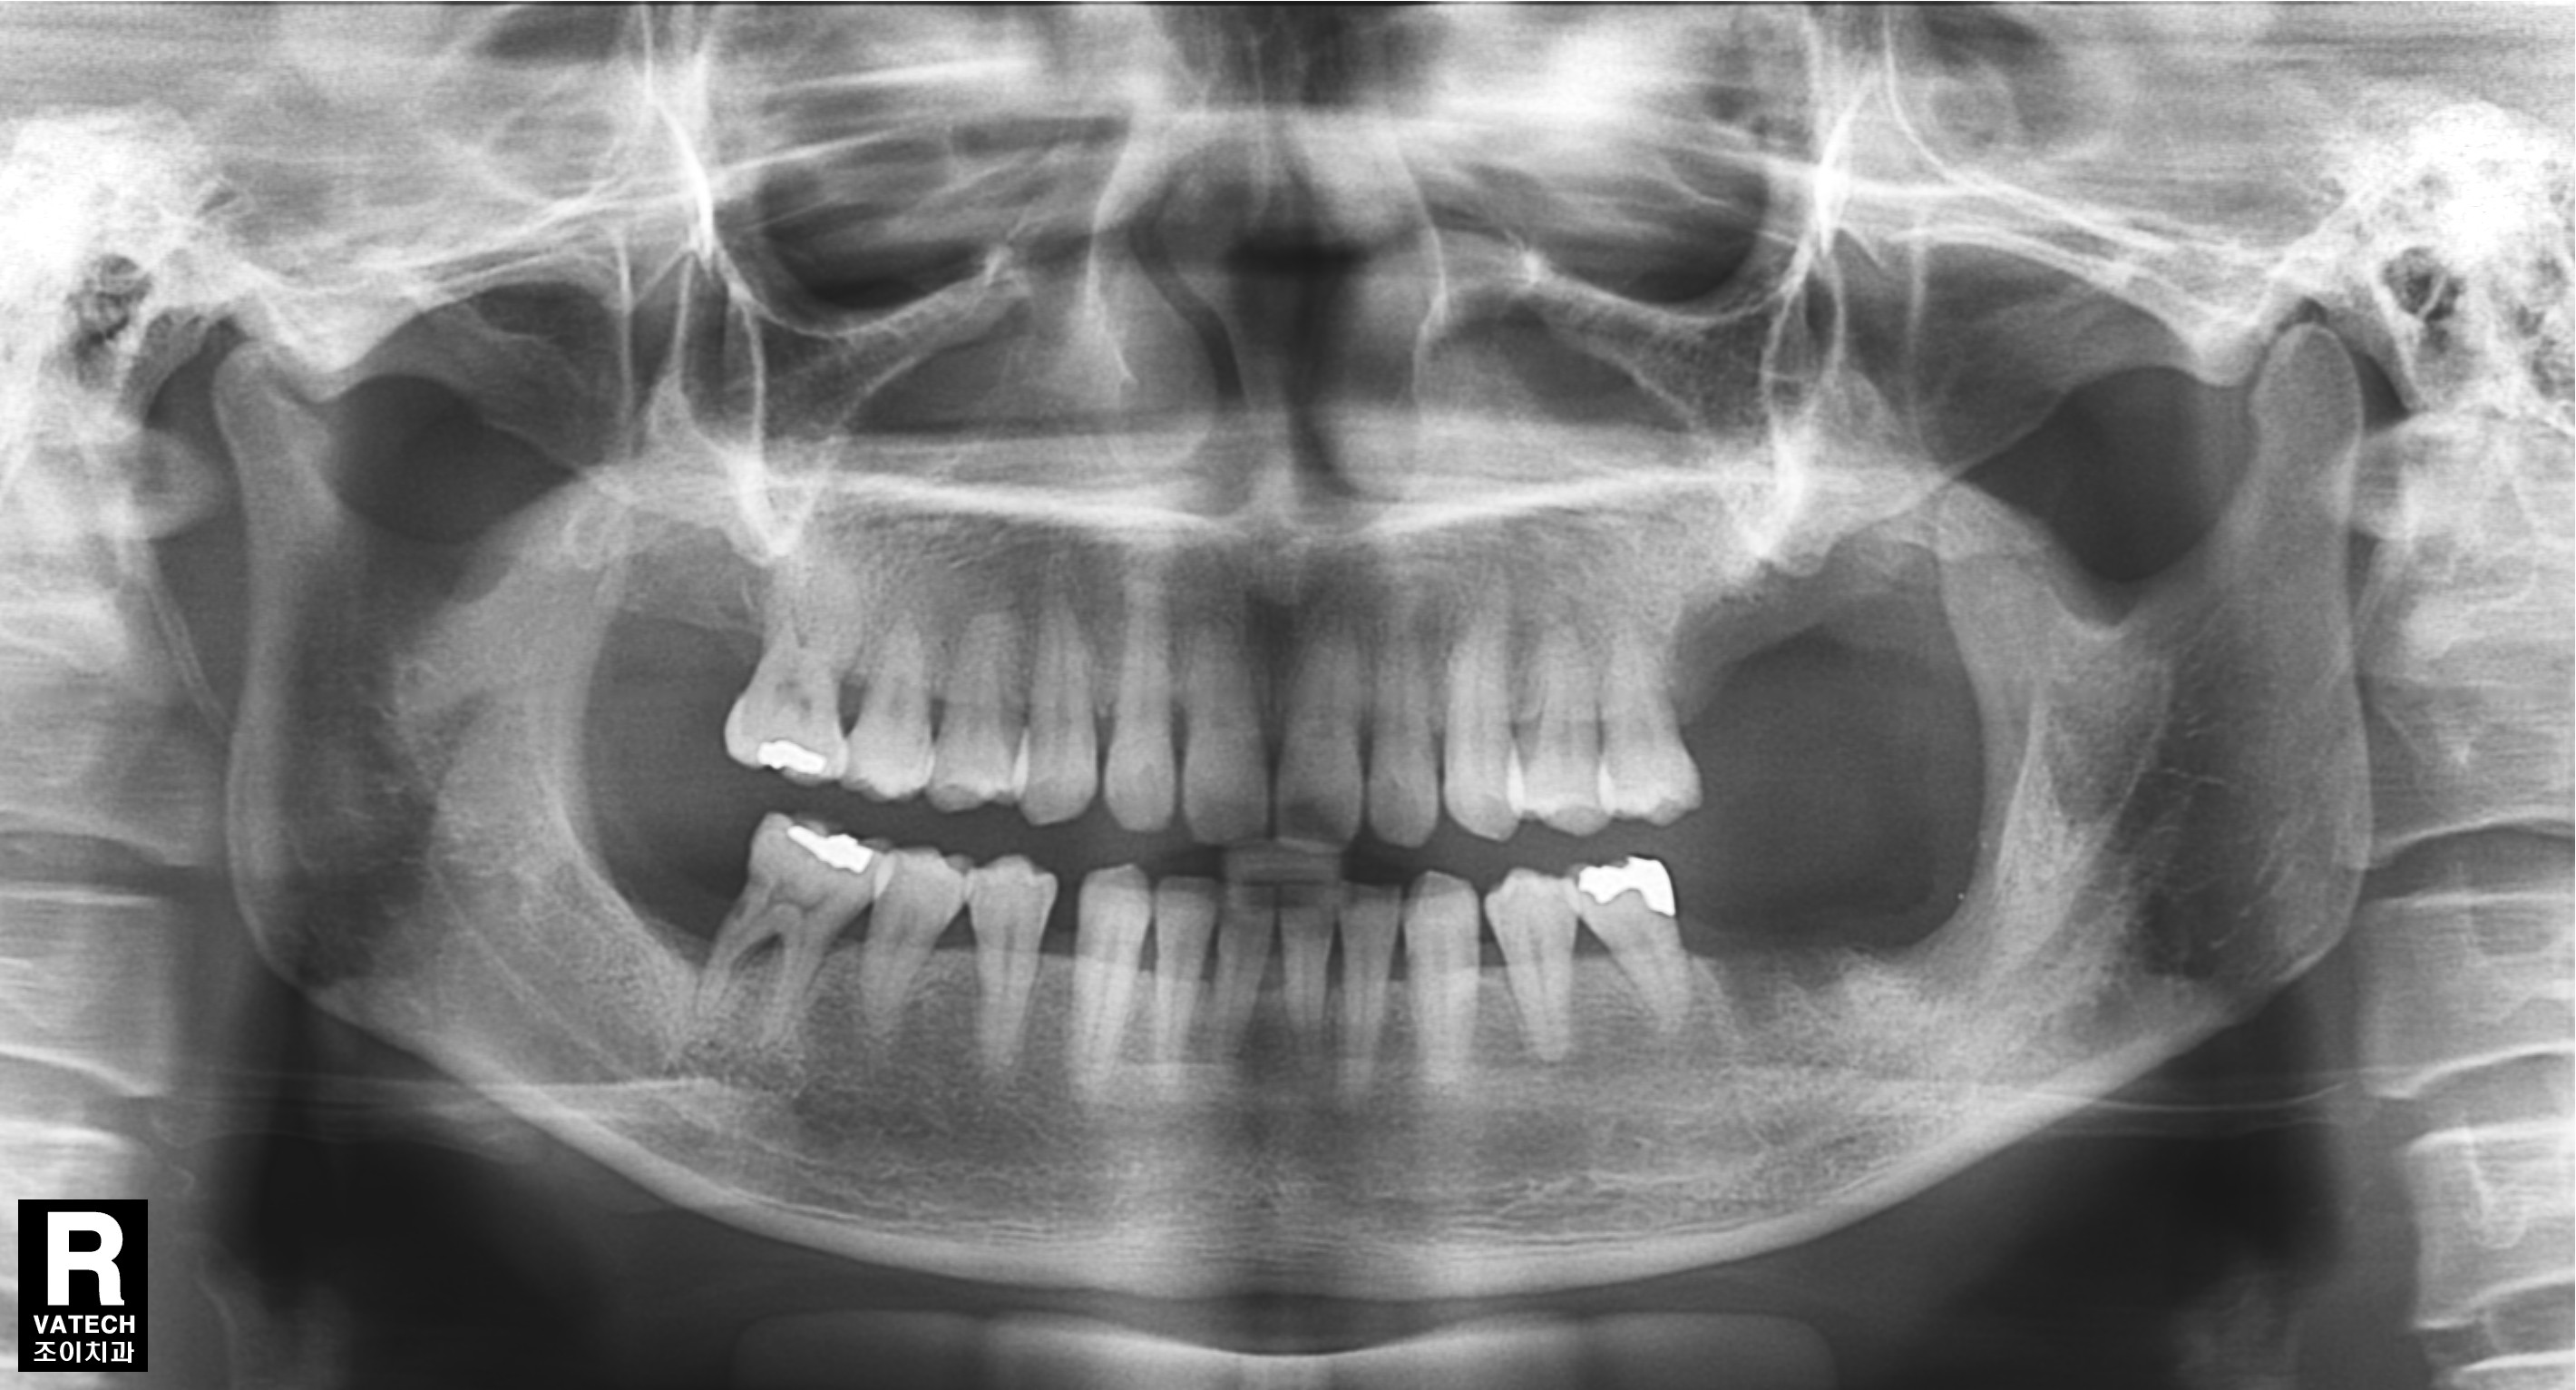

치주질환으로 치조골이 많이 녹아 내려간 경우 원하는 위치에 바로 임플란트를 심을 수 없는 경우가 많습니다.

또한 임플란트의 실패율도 높아집니다.

이 경우 골을 이식하는 것을 먼저 하고 수개월이 경과한 후에 다시 임플란트를 심어야 합니다.

그래야 원하는 위치에 임플란트를 심을 수 있고, 성공율을 높이며, 장기간 문제 없이 잘 유지할 수 있습니다.